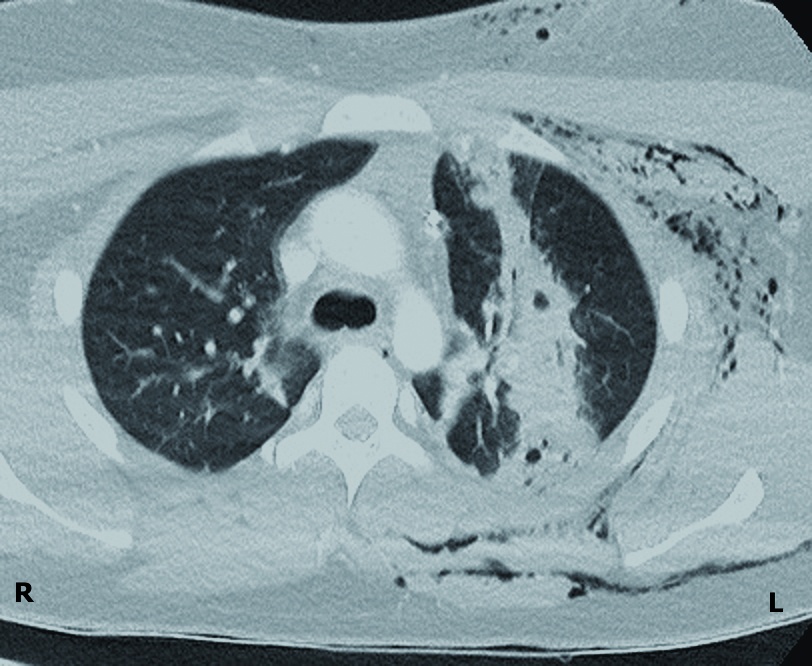

CT-Thorax

Die CT-Diagnostik zeigte eine sagittal verlaufende perforierende Verletzung des Lungenoberlappens links mit einer tiefreichenden Weichteilverletzung der ventralen Thoraxwand (Abbildung 2). Das Herz und die großen mediastinalen Gefäße waren unbeeinträchtigt. Ein Fremdkörper konnte auch CT-morphologisch ausgeschlossen werden.

Operative Therapie

Es wurde die Indikation zur notfallmäßigen Thorakoskopie (Video-Assisted Thoracic Surgery = VATS) links und zum Débridement im Bereich der Thoraxwand gestellt. Intrathorakal zeigten sich ein trübes, teils koaguliertes Gemisch aus Blut und Hydrauliköl sowie relevante Schmutzeinsprengungen mit Weichteilläsionen im Bereich der ventralen Eintrittswunde (Abbildung 3). Die dorsale Thoraxwand wies lediglich eine pleurale Läsion auf. Im linken Lungenoberlappen bestätigte sich die ventrodorsale Perforationsverletzung mit begleitender relevanter Einblutung, jedoch ohne Anhalt für eine aktive Blutung oder eine Fistelung (Abbildung 4).